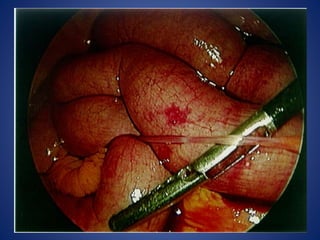

OPERATIVE MANAGEMENT

•REDUCING THE TERMINAL PART OF THE INTUSSUSCEPTION :

•REDUCING IS ACHIEVED BY SQUEEZING THE MOST DISTAL PART OF THE MASS IN

CEPHALAD DIRECTION